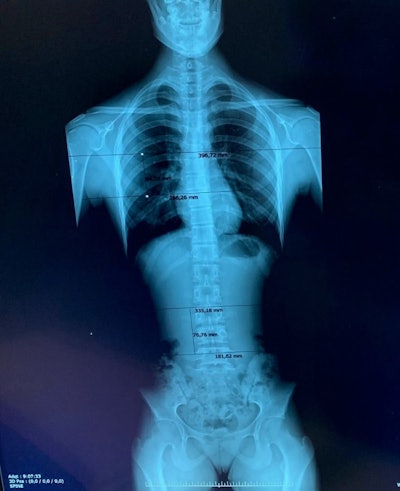

Reconstruction artifact in which a shift in part of the spine is shown. All figures courtesy of P. Garcia Castañon, S. Honorato Hernandez, C. Prieto Martin et al and ESR EPOS database.

Two- or three-phase x-ray machines are generally used, with a digital flat panel detector that moves down the spine, obtaining different images. Usually, two to three images are performed and a reconstructed full-spine image is created, they pointed out.

Estimated overlapping regions in the General Electric Definium 8000 unit for a patient with three projections.

Two systems are used to perform full spine studies at the Madrid hospital: a General Electric Definium 8000 machine and a Fuji FDR Smart Suspension system, which allows full-spine scans to be performed in one shot. For the latter, the detector consists of three regular detectors placed together, so there is no need to move the x-ray tube and detector down the spine, thus reducing artifacts and presumably patient effective doses due to non-overlapping.

In the study, 73 patients were imaged on the GE unit and 55 on the Fuji system. The entrance surface air kerma was calculated for each projection, from exposure and patient parameters manually recorded by the technologists during the studies. According to the images analyzed by the radiologists, a 6 cm region of overlap was considered between images for the conventional system.